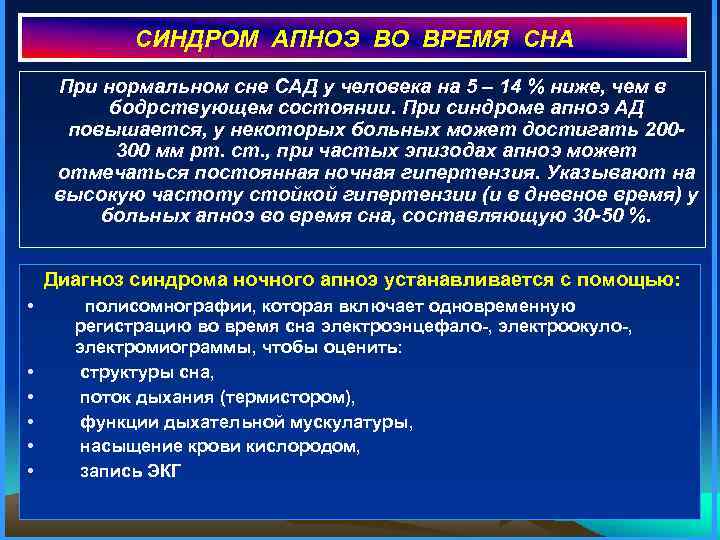

СИНДРОМ АПНОЭ ВО ВРЕМЯ СНА При нормальном сне САД у человека на 5 – 14 % ниже, чем в бодрствующем состоянии. При синдроме апноэ АД повышается, у некоторых больных может достигать 200300 мм рт. ст. , при частых эпизодах апноэ может отмечаться постоянная ночная гипертензия. Указывают на высокую частоту стойкой гипертензии (и в дневное время) у больных апноэ во время сна, составляющую 30 -50 %. Диагноз синдрома ночного апноэ устанавливается с помощью: • полисомнографии, которая включает одновременную регистрацию во время сна электроэнцефало-, электроокуло-, электромиограммы, чтобы оценить: • структуры сна, • поток дыхания (термистором), • функции дыхательной мускулатуры, • насыщение крови кислородом, • запись ЭКГ

СИНДРОМ АПНОЭ ВО ВРЕМЯ СНА При нормальном сне САД у человека на 5 – 14 % ниже, чем в бодрствующем состоянии. При синдроме апноэ АД повышается, у некоторых больных может достигать 200300 мм рт. ст. , при частых эпизодах апноэ может отмечаться постоянная ночная гипертензия. Указывают на высокую частоту стойкой гипертензии (и в дневное время) у больных апноэ во время сна, составляющую 30 -50 %. Диагноз синдрома ночного апноэ устанавливается с помощью: • полисомнографии, которая включает одновременную регистрацию во время сна электроэнцефало-, электроокуло-, электромиограммы, чтобы оценить: • структуры сна, • поток дыхания (термистором), • функции дыхательной мускулатуры, • насыщение крови кислородом, • запись ЭКГ